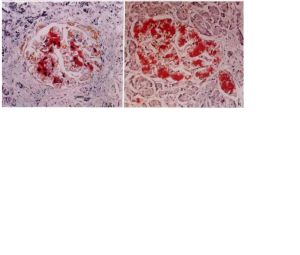

輕度:血液鐵濃度,雪鐵蛋白飽和度超過正常值, 無明顯臨床症狀(如在輸血量 超過5~10單位)。中度:組織臟器(心,肝)出現鐵沉積( 比如:輸血量 超過10~20單位)。

重度:臟器的結構改變(如肝纖維化硬化), 功能受損(如肝功能異常, 糖尿病)當輸血量 超過30~40單位時 發生。